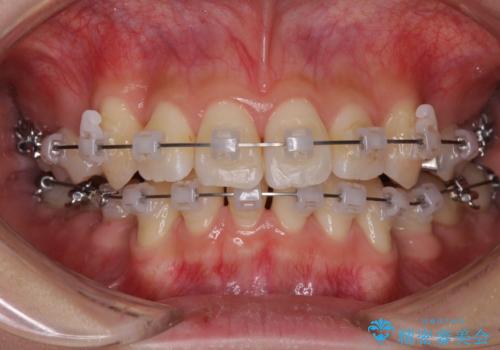

- 矯正装置

- クリアブラケット

20歳前後と年齢が若かったため、非常にスムーズに歯列が整い、1年半をかけずに治療を終えることができました。